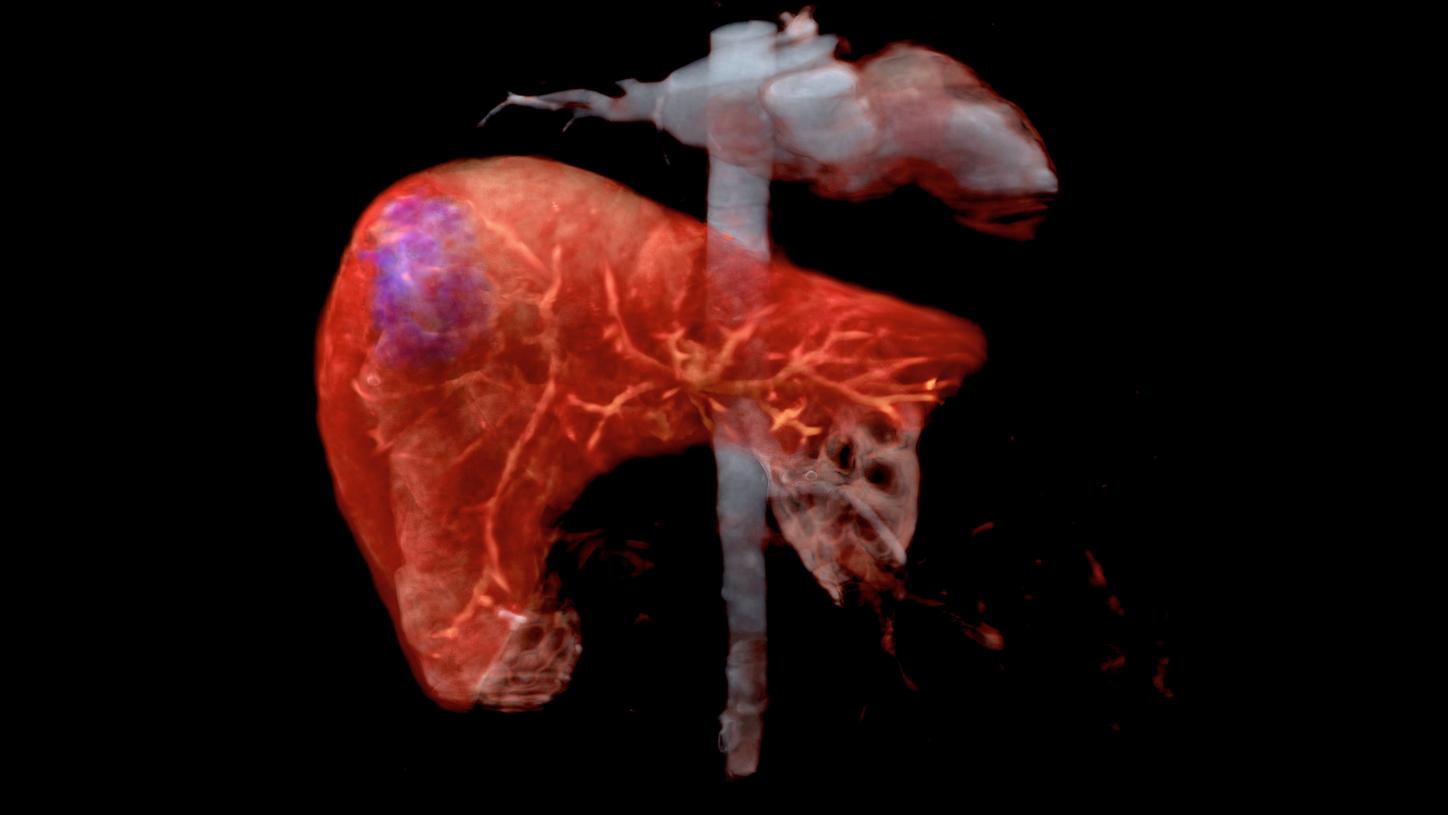

The influence of the medical image in healthcare is constantly growing. Diseases are detected earlier and treatments become more effective. When its usage is expanded beyond the field of diagnostics, entering the arenas of prevention and therapy, it can significantly contribute to lowering costs in healthcare on a global scale.